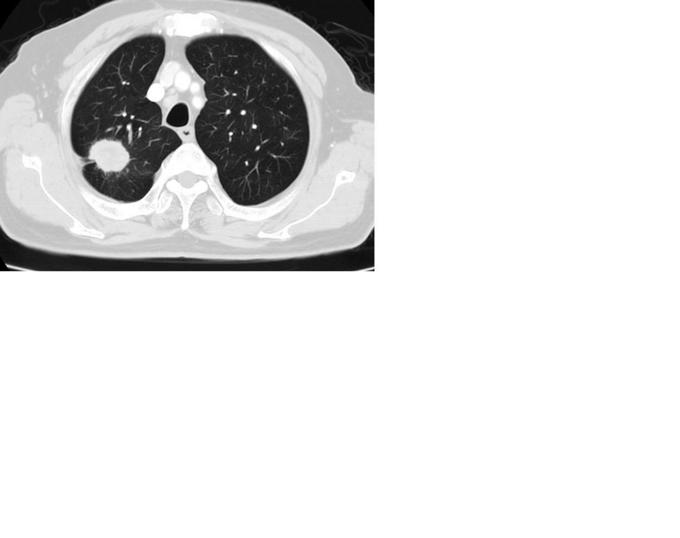

典型胸膜牵拉征

胸X线(2015-08-28,我院):右上肺可见团块状阴影

肺癌 治疗:手术切除